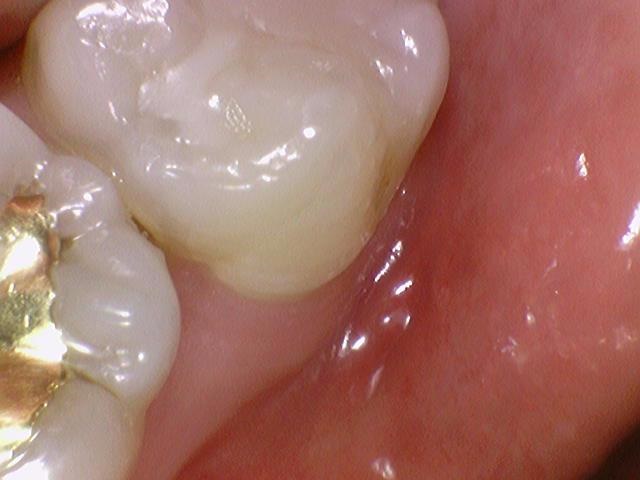

대부분의 치료해야하는 부위는 사진을 찍어서 직접 모니터로 보고 보여드립니다.

특히, 치아 속에 있는 충치는 눈으로는 보이지 않고, 엑스레이에서 볼 수 있는데요

오히려 이런 겉으로는 검게 보이지 않는 치아 속 충치가 더 위험합니다. 속에 위치하므로 더 깊기 때문이죠.

[아래 사진은 환자분이 공개에 동의한 사진입니다]

위 사진에서 치료가 필요한 충치가 보이시나요?

왼쪽처럼 겉에서는 멀쩡해보이는 치아도 파보면 충치가 있는 것을 확인할 수 있습니다.

위 사진에서 보듯이 왼쪽처럼 겉에서는 멀쩡해보이는 치아도 파보면 충치가 있는 것을 확인할 수 있습니다.

보여주는 치료.

이렇게 깊은 충치들을 사진을 찍어서 보여드리기 때문에 환자분들이 충치치료를 하고도

왜 충치가 안보이는데 치료를 했지? 라는 찝찝함을 없애드립니다.